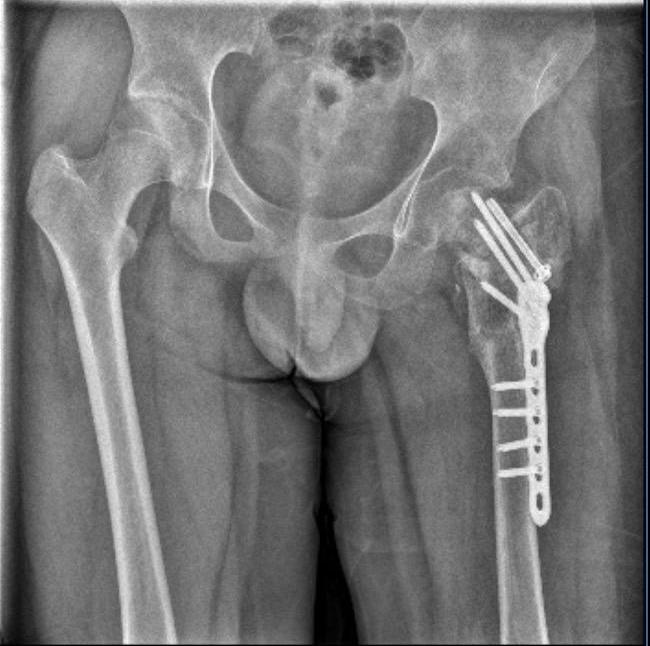

一家位于泉州的“四维成长基地”(简称四维基地),由自称“国家二级心理咨询师”向明胜担任校长, 招聘几名年轻人担任“教官”,号称“养育式成长教育模式实践基地”,专门招收青春期有“厌学、叛逆、网瘾、自残、逃学、打架”和狂躁、抑郁症等“成长障碍”的孩子。 2023年6月和8月,北方某市的武女士先后把14岁的双胞胎儿子大武、小武送到四维基地。她本以为孩子可以在心理辅导、体能训练的帮助下变得更好。没想到,9月7日,她接到小儿子骨折受伤的消息。 赶到泉州的武女士看到小武遍体鳞伤,多处陈旧性伤疤早已感染,耽误10多天的骨折造成孩子左髋部重伤二级。她称,治疗期间她得知,小武在基地中遭受了28天的虐待,“通宵罚站、跪举水盆、扇耳光、关小黑屋、殴打”等。她立即报警,向明胜支付了20余万元治疗费。 2024年,得知四维基地仍在扩大招生,武女士第二次报警。当年9月至10月,向明胜及三名教官先后被刑拘。2025年9月,本案在晋江市人民法院开庭,择日宣判。

四维成长基地大门,挂着“泉州市四维未成年人成长指导服务中心”牌子 图据受访人 “宣扬爱”的成长基地 大武、小武是双胞胎,均生于2009年。武女士是单亲妈妈,在两个孩子1岁时就离婚了。她舍不得兄弟俩分开,争取了两个孩子的抚养权。 武女士告诉红星新闻,大武在北方老家上私立中学时,在宿舍遭到霸凌,由于领头孩子也是单亲家庭,家长还诚恳道歉,武女士选择了原谅。但大武却受到刺激,开始逃学,学会抽烟喝酒,还曾试图跳河自杀。 为了不让大武堕落,经朋友介绍,2023年6月21日,她把大武送到泉州四维成长基地。“我觉得这个学校挺干净,装修也好,十几个学生,加上五六个教职工,人不多,也好管理。” 记者看到四维基地的招生宣传册称,通过“读、练、教、爱、化”五种方式进行“潜移默化,身体力行”的养育式成长教育。其中“爱”是指“爱的唤醒、爱的接纳、爱的植入、爱意浸润、爱意延续、爱心传递”。 50天后的8月11日,武女士带小武去泉州看哥哥。交谈中,向明胜得知武女士是单亲妈妈,小武不好好学习,就劝说她把小武也留下。“单亲家庭长大的孩子有硬伤。你小儿子的心理问题非常严重,必须留下来矫正一下。” 那次,武女士在学校住了一晚,大武极力劝阻,“你别把弟弟放到这里,里面很苦,弟弟吃不了这个苦,他肯定会出事。”但武女士不听。 后来武女士一直自责,当时带小武去泉州,是把他“骗去”的。她按照向明胜的指导,没跟小武告别,偷偷离开了基地。 由于基地实行封闭式管理,学生一入校就被收缴手机,武女士无法与儿子联系。她在微信上询问孩子的情况,向明胜表示“挺好的”。 9月7日,向明胜打电话给武女士,称小武“骨折了,但没有很大影响”。武女士很着急,要求将小武送到医院。向明胜拒绝了。直到9月9日武女士赶到泉州,才把儿子送到泉州市正骨医院。“医生说,这已经是陈旧性骨折了。”  目前在北方老家康复治疗的小武 图据受访人 在医院,武女士看到小武面黄肌瘦,遍体鳞伤,情绪崩溃了。其间,大武来医院,告诉她弟弟在基地里遭受体罚,她才报警。 “用脚踹”的成长基地 武女士告诉红星新闻,小武基本上健康,在北方老家上私立学校,每学期都要提交体检报告才能住宿。但他小时候做过心脏手术,体质弱。在四维基地跟不上体能训练,于是每天遭到体罚。 小武告诉红星新闻,四维基地的日常课程很简单:早起到操场跑10圈,然后打扫卫生,吃早饭;上午体能训练,然后吃午饭;下午上一节心理辅导课,接着跑30圈,然后吃晚饭;晚上接着跑圈,10点睡觉。没有周末,但周日跑的少一些。 他向记者回忆,第一次下午跑30圈,他跑不动,教官“连拖带拉”逼着他跑。“晚饭前,我还没开吃就呕吐了。”晚上教官拉着他接着跑。几天后,小武跑步时摔倒,动不了,吃饭前,他只能在地上往前爬。向明胜认为他是“装的”,让四五个人把他拖到食堂,导致他大腿一侧脱了一层皮。此后,他常被嫌跑太慢,当他说膝盖疼,就会被说“装的”,然后遭到校长、教官的踢踹。 小武说,8月底一天,校长嫌小武跑太慢,让教官拿绳子拴在皮带上,拉着他跑。后来他腿软摔跤,感觉腿骨折了一下,很疼。“同学告诉教官和校长,校长走过来,直接往我疼的地方猛踹了几脚。” 这次骨折,没能引起重视。小武说,那天下午,他一直趴在操场上,吃饭时,他被几个人拖到食堂,被禁止吃饭,然后又被拖回操场,又连续遭到踢踹。  小武的膝盖伤痕 图据受访人 小武说,骨折后,他上厕所蹲不下去,教官发现后,让其他人把他拖到操场,罚他在太阳底下跪着,然后光脚站立。他还被禁止扶墙,因此无法去厕所,有次尿了裤子,教官让一群人把他拖出来,按在地上。“他们让我站在操场上。他们站成一圈围观。” 在此期间,向明胜曾找来一个诊所中医,给小武检查,对方看了一下后告诉向明胜,“要么是骨折,要么就是装的”。向更认为小武是装的。 此外,小武先后三次被关进一个由楼梯储物间改造的“小黑屋”。“第一次是因为跑得慢,后面两次是骨折后没法跑步。关了一下午才放出来。”小武说,最后一次,他被罚跪在小黑屋里,向明胜亲自看管,“不给我水喝。”大武告诉红星新闻,弟弟曾被连续罚站三天三夜。 小武称,9月6日,他遭受了最残酷、最漫长的一次虐待。早上,向明胜踹门进宿舍,让他去教室,因无法上楼,他被要求15分钟内爬上三楼。爬上去后,他被要求跪着举凳子,凳子掉下,教官就踢一脚,午休时也不能停。下午,他被拖到操场,他被要求举水盆,“水洒了,教官就踹我;然后继续让我跪。” 他说,晚上,教官让他继续举水盆。因疲劳和瞌睡,他倒了几次,每次都被校长、教官踢踹。中途,他被要求站起来,因地滑又摔了一跤。后半夜,向明胜让他一直跪着,“他问我问题,我一说话,他就扇我脸。我说疼,他问我哪儿疼,我给他指腰胯,他就往我那儿猛踹。另一个教官也踹了我胸口。” 小武说,他被虐待了一天一夜,一直跪到7日天亮。第二天,为了“戳破我的谎言,让我死心”,向明胜带小武去镇卫生院拍了片子,“片子显示是骨折,他立马变了一副面孔,给我妈打电话。”  小武左股骨陈旧性骨折,打了钢针、钢板 图据受访人 小武说,他的多处伤口都是在太阳下的水泥地上拖行造成的。“流血后,脚后跟起了两个水泡,教官给我戳破,简单消毒后就不再管。”他的伤疤,多次反复结痂。 武女士见过那几个打人的教官,“都是年轻小伙。”她曾询问医生,为什么孩子的伤会这么严重,医生说,小武一开始摔倒,并不严重,但后来多次遭踢踹,导致骨折,加上频繁的罚跪、拖行,导致各处伤口越来越严重,并感染。 “披外衣”的成长基地 “四维成长基地”并非正式注册的机构。其招生宣传手册显示,地址为福建省晋江市英林镇嘉排村林厝区135号。天眼查显示,以该地址注册的公司为“泉州市泉芯心理咨询有限公司”,法人代表是向明胜,注册于2023年4月,于2024年9月27日注销。 教职工小孟告诉红星新闻,这家心理咨询公司只是向明胜为了“规避监管”而设置的一个“外壳”。实际上,四维基地从2022年就开始运营。 武女士告诉红星新闻,第一次到四维基地后,她对这里产生信任是源于两点。一是,校长向明胜是国家二级心理咨询师,她希望他可以给大武做一些心理矫正和疏导;二是基地大门柱子上挂了一个“泉州市四维未成年人成长指导服务中心”(简称四维成长中心)的牌子,她上网查了一下,据称该中心系泉州市民政局主管,“政府办的,肯定正规,我放心。” 天眼查显示,四维成长中心成立于2022年8月,登记和主管单位是泉州市民政局。 红星新闻咨询泉州市民政局未成年人救助保护中心,工作人员表示,2022年,民政局确实批准过四维成长中心,性质是社会公益组织,地点在泉州市鲤城区百脑汇商厦,业务范围是开展“困境儿童日常帮扶与关爱援助”。工作人员称,“我们并没有批准他们成立什么矫正学校、教育基地,也不知道他们跑到晋江的村里建了这个基地。”2024年,民政局发现该中心“银行账户长期为0,没有活动迹象”,要求其关闭了。 然而此后,四维基地仍继续招生运营。2024年,武女士听一名家长说,基地里的孩子更多了,有孩子“因为逃跑被吊着打”。武女士再次报警。 7月,晋江市公安局对小武被故意伤害一案立案侦查。随后,晋江市公安局对小武进行了人体损伤程度鉴定,8月29日出具的《鉴定意见通知书》显示,小武三个部位不同程度损伤,其中,“左髋部重伤二级,胸部轻伤一级,双下肢轻微伤”,同时,其左股骨打了钢针、钢板。 同年9月14日,向明胜因涉嫌过失致人重伤罪,被晋江市公安局刑拘,次日取保候审,10月19日,晋江警方再次将向明胜刑拘。10月中旬至下旬,何某坡、张某宇、洪某鑫三名老师也先后被刑拘。 2025年9月,经晋江市检察院公诉,向明胜涉嫌故意伤害罪和虐待被监护、看护人罪两起罪名,何、张、洪三名教官涉嫌虐待被监护、看护人罪一案,在晋江市法院开庭审理。 红星新闻实习记者 陈龙 记者 刘木木